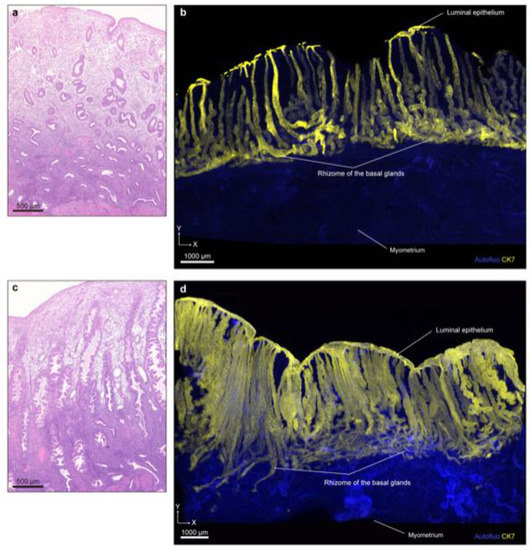

| Tempest et al. [28] (2020) | Human | Digital reconstruction of serial pathological section images (4 µm × 100 slices) | 3D visualization of part of the glands(Pathological sections included full-thickness of the endometrium) | The deeper basalis glands demonstrated a complex, often branched organization, enveloping one another horizontally in a mycelium/root-like configuration on the underlying myometrium. |

| Yamaguchi et al. [29] (2021) | Human | Tissue clearing (updated CUBIC protocol IV) of normal human uterine tissues (about 5–15 mm square), light-sheet microscopy | Full-thickness of the endometrium | The basal glands formed the rhizome structure, that is, a horizontally expanding plexus morphology. Some glands shared the rhizome with other glands. |